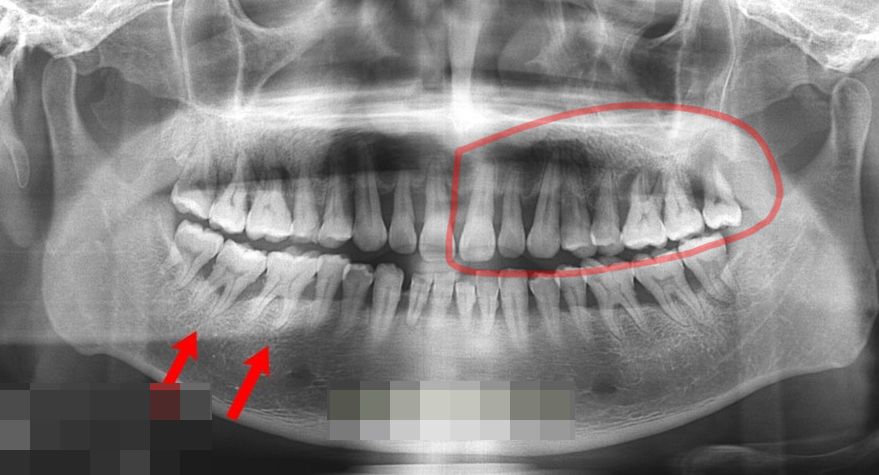

현재 한번 방문으로 붉은색 영역부분만 치료 받았습니다.